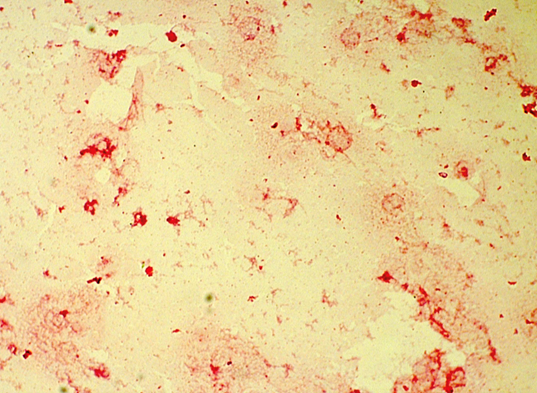

- Blood cultures returned positive for Haemophilus influenzae (beta-lactam positive) in two sets at 13 and 18 hours. (Figure 1)

Figure 1. Haemophilus influenza in a blood culture5